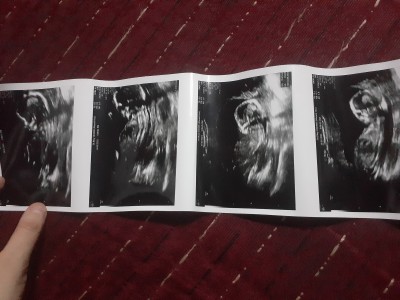

Kızlar 13+5 haftalık gebeyim bugün kontrolüm vardı doktor duruşu hareketleri erkeğe benziyor dedi ama yinede kesin birşey diyemem dedi bir sonraki gelmene kesin olur dedi

Erkek gibi sanki.

Oğlumun ultrason kagidina ayni benziyo birde haftasina göre büyük duruyo yada fotoda ole

Banada erkek gibi geldi

Bence kız dudakları dolgun olacak sanki<3

Erkek geçti icimden hayırlısı olsn

Erkek diyesim geldi